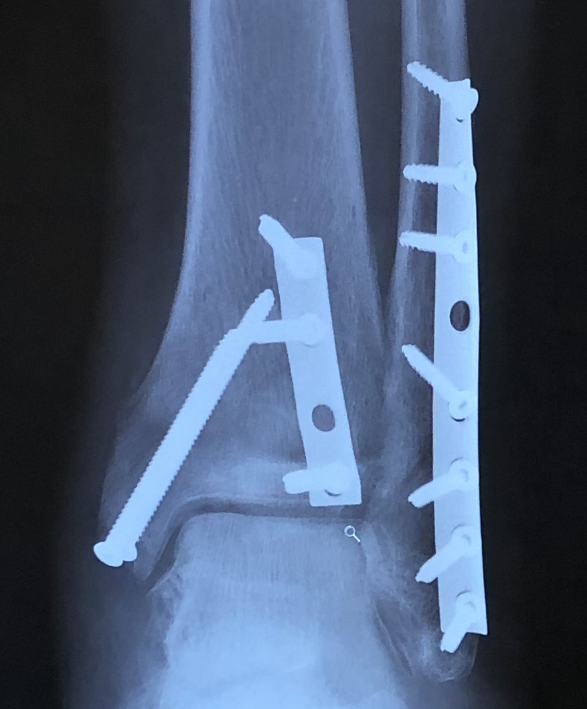

After sustaining a trimalleolar fracture of my left ankle on July 15,2020, Dr. David S. Levine came highly recommended. After my first appointment, he exceeded all trustworthy expectations. Dr. Levine and his (PA) Lauren Buchwald took the time to answer all my questions.